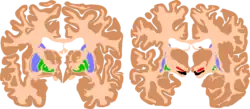

| The basal ganglia plays essential roles in voluntary motor function. Various forms of damage to the basal ganglia can cause a range of movement disorders. | |

Like other forms of CP, it is primarily associated with damage to the basal ganglia in the form of lesions that occur during brain development due to bilirubin encephalopathy and hypoxic–ischemic brain injury.[7]

CP in general is a non-progressive, neurological condition that results from brain injury and malformation occurring before cerebral development is complete.[3] ADCP is associated with injury and malformations to the extrapyramidal tracts in the basal ganglia or the cerebellum.[7] Lesions to this region principally arise via hypoxic ischemic brain injury or bilirubin encephalopathy.[7]

Hypoxic-ischemic brain injury is a form of cerebral hypoxia in which oxygen cannot perfuse to cells in the brain. Lesions in the putamen and thalamus caused by this type of brain injury are primary causes of ADCP and can occur during the prenatal period and shortly after.[7] Lesions that arise after this period typically occur as a result of injury or infections of the brain.[18]

Bilirubin encephalopathy, also known as kernicterus, is the accumulation of bilirubin in the grey matter of the central nervous system. The main accumulation targets of hyperbilirubinemia are the basal ganglia, ocular movement nucleus, and acoustic nucleus of the brainstem.[7] Pathogenesis of bilirubin encephalopathy involves several factors, including the transport of bilirubin across the blood–brain barrier and into neurons.[7] Mild disruption results in left cognition impairment, while severe disruption results in ADCP.[7] Lesions caused by accumulation of bilirubin occur mainly in the global pallidus and hypothalamus.[7] Disruption of the blood–brain barrier by disease or a hypoxic ischemic injury can also contribute to an accumulation of bilirubin in the brain.[7] Bilirubin encephalopathy leading to cerebral palsy has been greatly reduced by effective monitoring and treatment for hyperbilirubinemia in preterm infants.[7] As kernicterus has decreased due to improvements in care, over the last 50 years the proportion of children developing athetoid CP has decreased.[19] In most cases, will have normal intelligence.

Magnetic resonance imaging (MRI) is used to detect morphological brain abnormalities associated with ADCP in patients that are either at risk for ADCP or have shown symptoms thereof.[6] The abnormalities chiefly associated with ADCP are lesions that appear in the basal ganglia.[6] The severity of the disease is proportional to the severity and extent of these abnormalities, and is typically greater when additional lesions appear elsewhere in the deep grey matter or white matter.[6] MRI also has the ability to detect brain malformation, periventricular leukomalacia (PVL), and areas affected by hypoxia-ischemia, all of which may play a role in the development of ADCP.[4] The MRI detection rate for ADCP is approximately 54.5%, however this statistic varies depending on the patient's age and the cause of the disease and has been reported to be significantly higher.[7]

Multiple classification systems using magnetic resonance imaging (MRI) have been developed, linking brain lesions to time of birth, cerebral palsy subtype and functional ability.[23][24][25][26] Around 70% of patients with DCP show lesions in the cortical and deep grey matter of the brain, more specifically in the basal ganglia and thalamus. However, other brain lesions and even normal-appearing MRI findings can occur, for example white matter lesions and brain maldevelopments.[2][25][27][28] Patients with pure basal ganglia and thalamus lesions are more likely to show more severe choreoathetosis whereas dystonia may be associated with other brain lesions, such as the cerebellum.[2] These lesions occur mostly during the peri- and postnatal period since these regions have a high vulnerability during the late third trimester of the pregnancy.[29] Unfortunately, contemporary imaging is not sophisticated enough to detect all subtle brain deformities and network disorders in dystonia. Research with more refined imaging techniques including diffusion tensor imaging and functional MRI is required.[10][30]